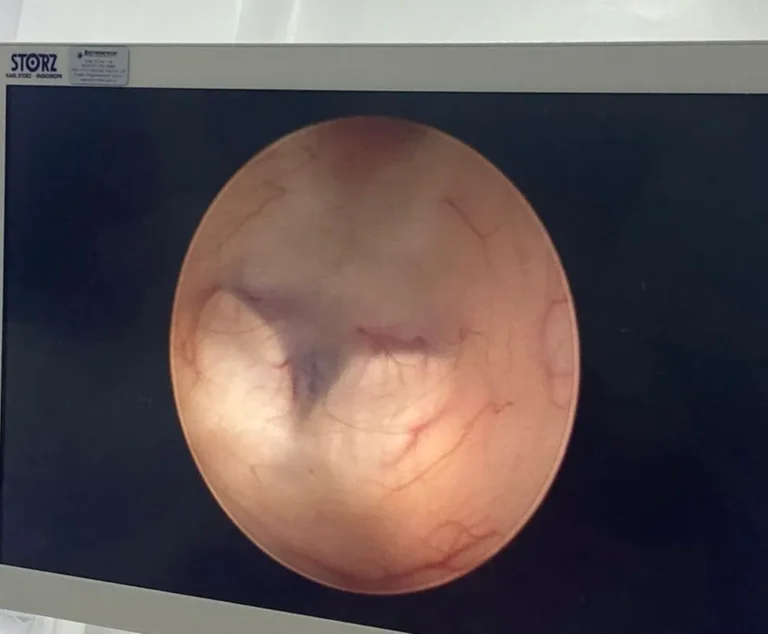

- ✔ Endoscopic Brain Surgery

- ✔️ Endoscopic brain surgery